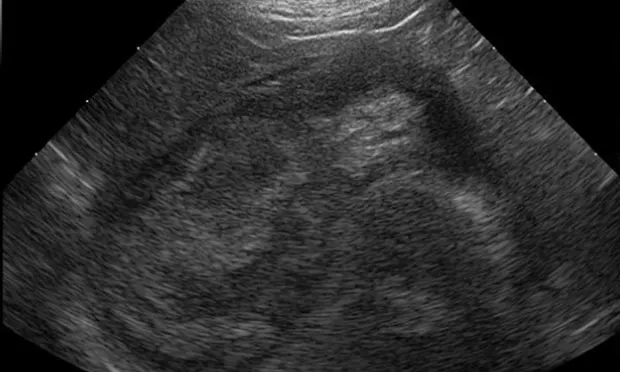

• Immobile echogenic material can be visualized in the gallbladder lumen, often with a characteristic finely striated or stellate (kiwi-fruit) appearance.

Featured Image

Figure 1A

In this ultrasound, the gallbladder contents show a broad hypoechoic region at the periphery that corresponds to the mucosal layer. The central echogenic bile forms a stellate pattern with a distinct border between the hypoechoic and hyperechoic regions. The gallbladder contents were immobile when the patient was repositioned.

• Abdominal ultrasonography is a sensitive and definitive test for GBM (See Figure 1)